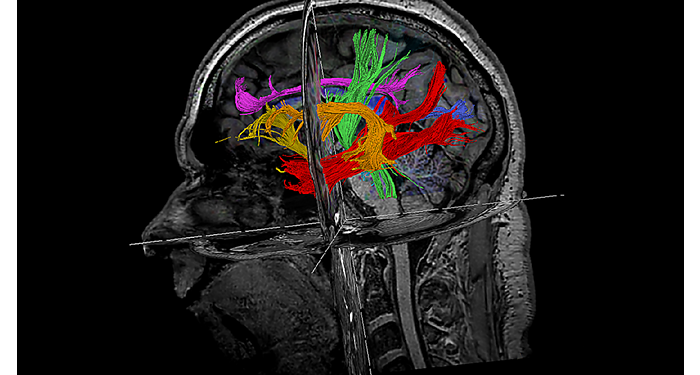

El 70% de los radiólogos consideran que las indicaciones neurológicas son un desafío, sobre todo debido a la falta de técnicas apropiadas de imagenología y visualización¹. Philips tiene como objetivo proporcionar la mejor claridad de diagnóstico posible y orientación terapéutica para todos los pacientes con trastornos neurológicos. Al aprovechar nuestra plataforma digital dStream, este año presentamos un conjunto de estrategias nuevas de imagenología y visualización. Esto puede ayudarlo a resolver preguntas sobre neurología complejas con mayor certeza, así como a desbloquear nuevos territorios neurológicos en aplicaciones neurofuncionales avanzadas. Este es un paso clave para aumentar el diagnóstico neurológico y, en última instancia, impactar más vidas con la RM. ¹ TMTG Market Survey 2016

Nuevas aplicaciones neurológicas

En Philips, creamos innovaciones de IRM que son importantes para personas reales: los radiólogos encargados de hacer más, mejor y más rápido, los médicos que requieren resultados confiables para hacer diagnósticos confiables, los investigadores que buscan respuestas a preguntas consecuentes y los pacientes que anhelan una experiencia más sencilla y respuestas directas.